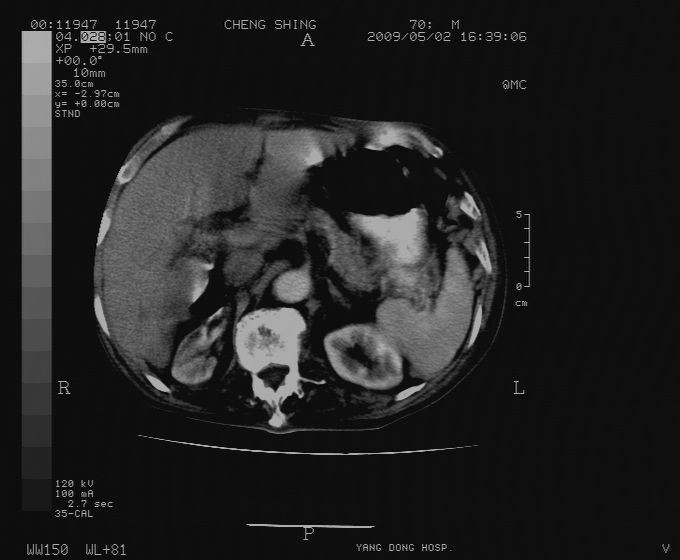

标题: CT19743:男70岁,肺部疾病入院,B超发现肝右叶占位,CT [打印本页]

标题: CT19743:男70岁,肺部疾病入院,B超发现肝右叶占位,CT

肝表面塌陷,病灶周围有子灶,前面较大子灶强化符合肝癌表现,考虑肝癌肝转移可能性大.

1.考虑肝癌肝转移

2.两侧胸水,左下肺不张!

1)考虑肝癌并肝内转移。2)少量腹水。3)双侧胸腔积液。

1)考虑肝癌并肝内转移。2)少量腹水及双侧胸腔积液。3)椎体退变。